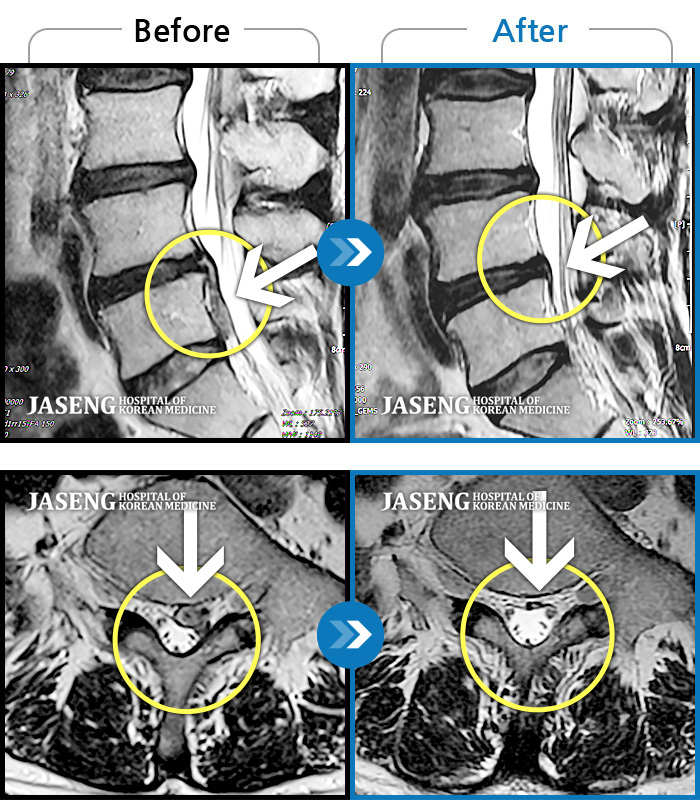

MRI 치료사례

좌측 허리와 골반이 아프고, 좌측 다리에 통증과 저림이 있었다.